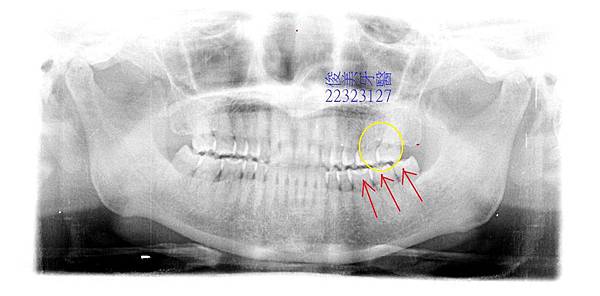

醫師判斷牙周囊袋已太深,因咬合問題造成牙周破壞,牙齒齒軸不正、對咬的角度不好,長期

累積傷害,一旦出現症狀後就很難斷根,最後會演變為牙周病拔牙。

因只要上下牙齒一對合,就攻擊牙縫處,直接將食物衝擊到牙齦處,導致牙齦發炎,牙周反覆受到傷害。